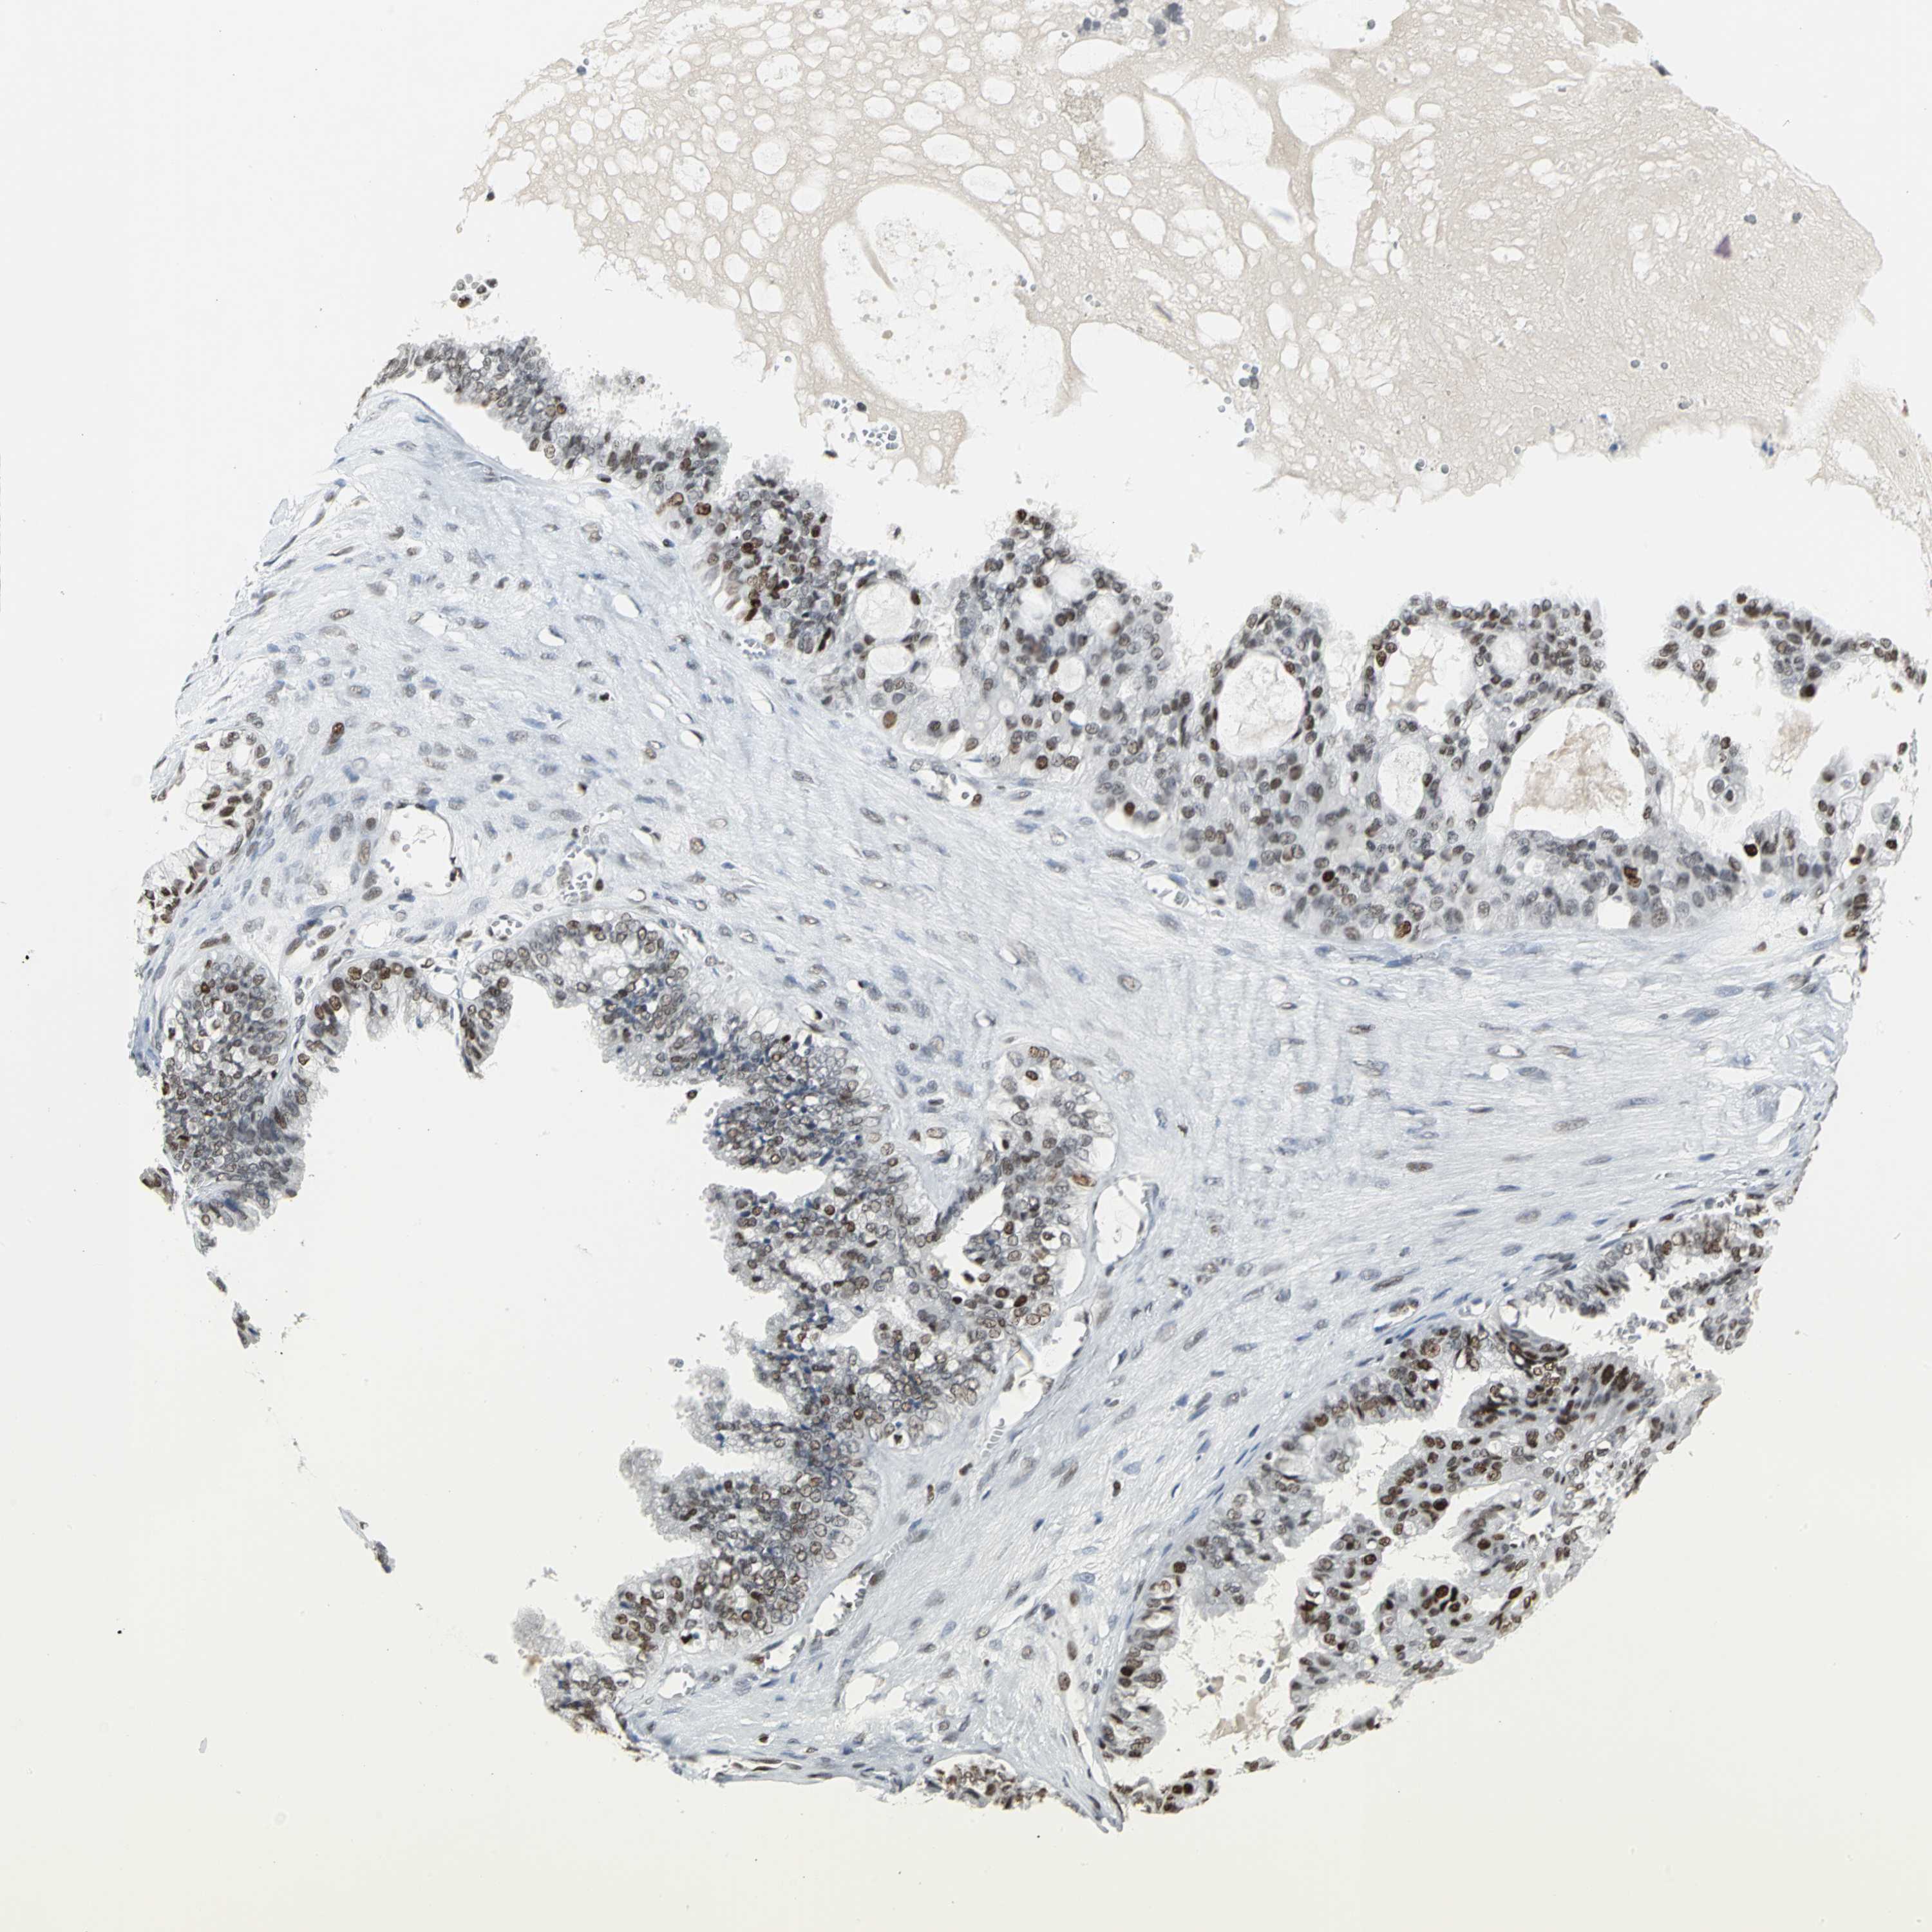

OVARIAN CANCER - Protein expressioni

A mouse-over function shows sample information and annotation data. Click on an image to view it in a full screen mode. Samples can be filtered based on level of antibody staining by selecting one or several of the following categories: high, medium, low and not detected. The assay and annotation is described here.

Note that samples used for immunohistochemistry by the Human Protein Atlas do not correspond to samples in the TCGA dataset.

Antibody stainingi

Antibody staining in the annotated cell types in the current human tissue is reported as not detected, low, medium, or high, based on conventional immunohistochemistry profiling in selected tissues. This score is based on the combination of the staining intensity and fraction of stained cells.

Each image is clickable and will lead to virtual microscopy that enables deeper exploration of all samples and also displays staining intensity scores, fraction scores and subcellular localization as well as patient and tissue information for each sample.

Antibody HPA004911

Staining

High

Medium

Low

Not detected

Intensity

Strong

Moderate

Weak

Negative

Quantity

>75%

75%-25%

<25%

None

Location

Nuclear

Cytoplasmic/membranous

Cytoplasmic/membranous,nuclear

Carcinoma, endometroid

Carcinoma, NOS